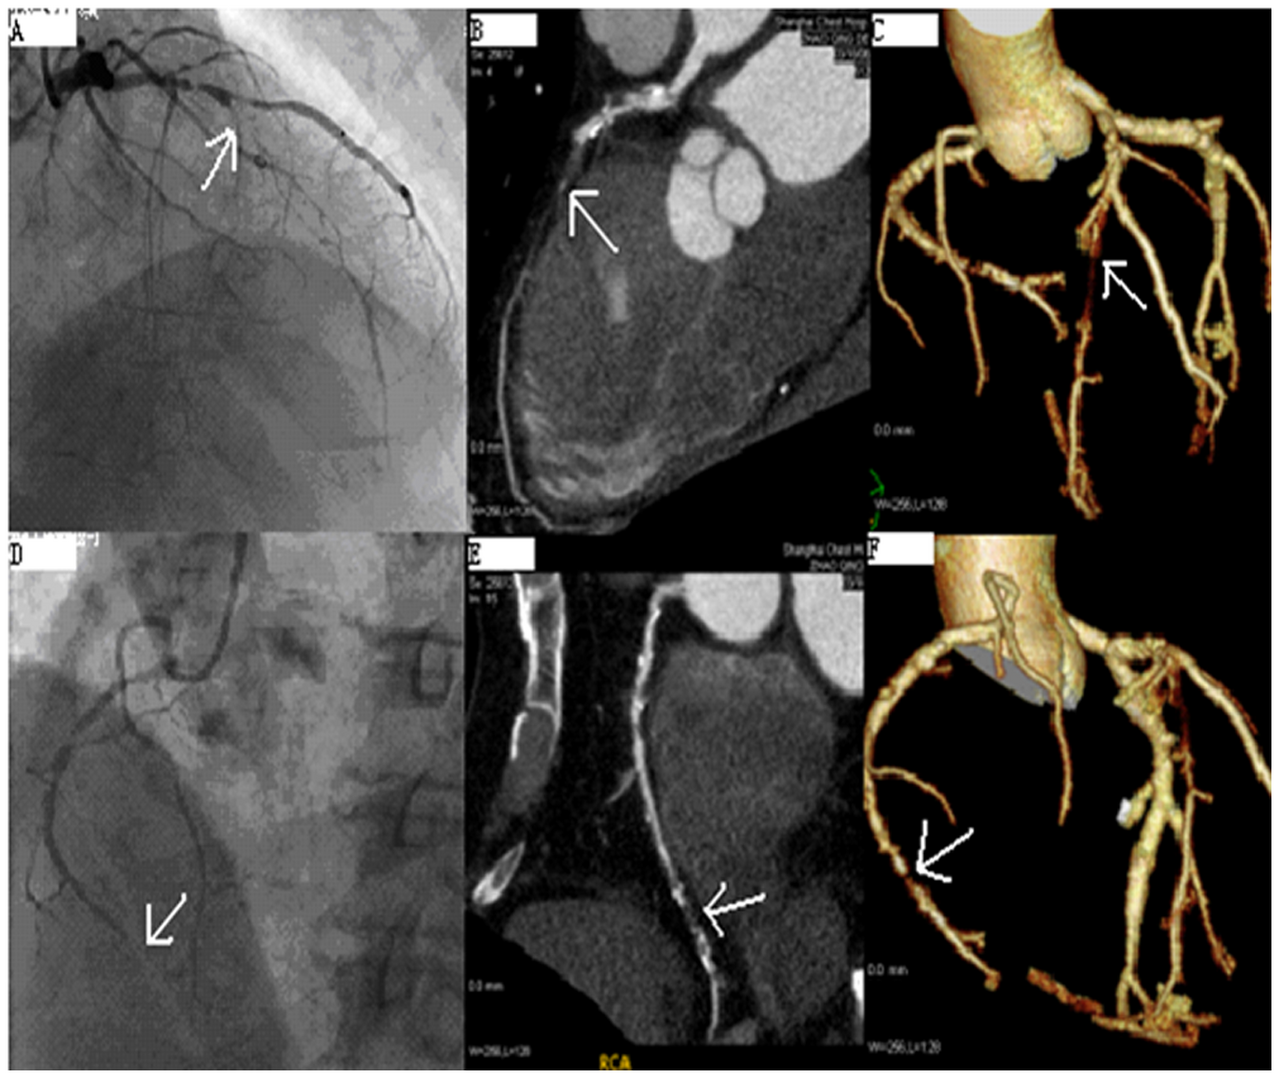

Cardiac phantom with myocardium, chambers, valves, and coronary arteries

AI-generated comprehensive cardiac phantom with all four chambers, valves, coronary arteries, great vessels,...